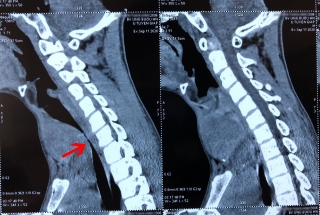

Bệnh viện Ung Bướu Hà Nội vừa thực hiện thành công ca phẫu thuật phức tạp cho một bệnh nhi mắc ung thư tuyến giáp di căn phổi hiếm gặp. Trước mổ, bệnh nhân bị khối u lớn chèn vào đường thở gây nguy hiểm đến tính mạng.